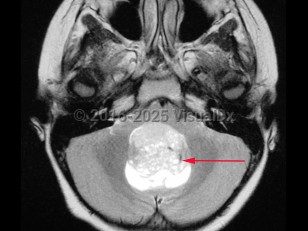

Medulloblastoma in Adult

A medulloblastoma is a malignant primary brain tumor located in the posterior fossa near the fourth ventricle. It is the most common malignant brain tumor in children. One-third of cases present in children aged younger than 3 years. In adults, the tumor usually presents before age 40.

Initial symptoms may relate to increased intracranial pressure as a consequence of blockage of the fourth ventricle, causing morning headache, nausea / vomiting, and irritability. Later, patients can develop ataxia, frequent falls, papilledema, diplopia, nystagmus, and/or neck stiffness.